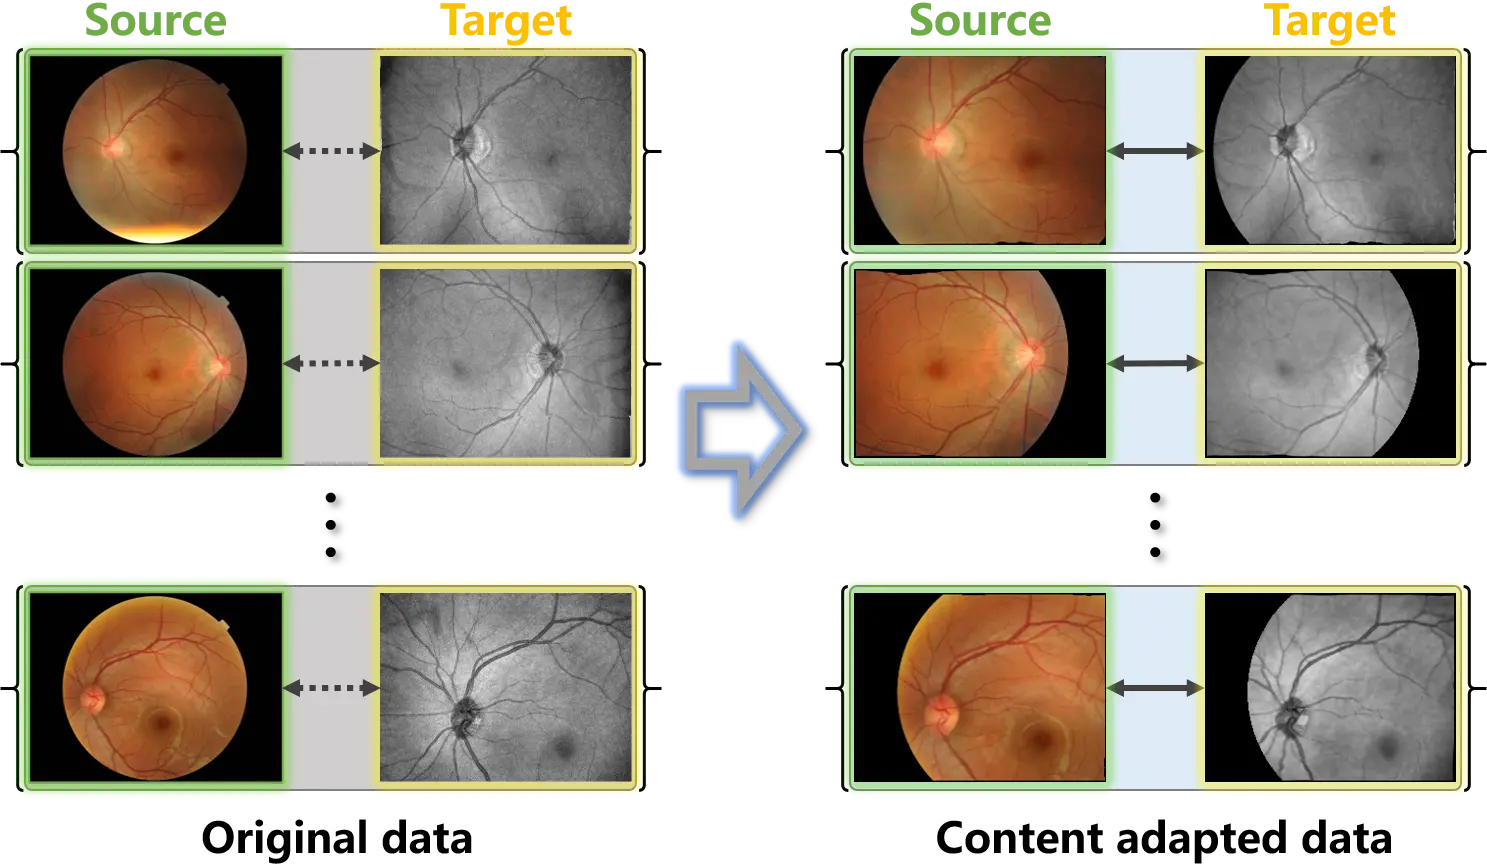

The proposed content adaptation constructs paired samples from unpaired (weakly paired) data to correct the distribution bias. As illustrated in Figure 3, the proposed method consists of two stages: content matching and adaptive sampling.

Figure 3. Workflow of content adaptation on weakly paired and unpaired data. Content adaptation consists of content matching and adaptive sampling. The content matching registers the source and target samples to align the data spaces, and the adaptive sampling corrects the distribution bias by symmetrically collects samples from the aligned data spaces.

Through content matching and adaptive sampling, paired samples are constructed from the weakly paired and unpaired data. Content adaptation corrects the distribution bias in the original data, since aligned distributions are provided in the paired samples. As demonstrated in Figure 2b, the distribution bias in the image space of the weakly paired 2D data and the scan sampling from the unpaired 3D data are corrected using content adaptation. Specifically, the deformable registration algorithms proposed in our previous study[30] and advanced normalization tools (ANTs)[31] are separately introduced to conduct content matching. For ANTs-based registration, an ElasticSyN deformable transformation is adopted, together with a multi-resolution optimization strategy with four iteration levels. Nearest-neighbor interpolation is applied when warping images to preserve discrete anatomical structures.

Figure 4. Examples of the original weakly paired retinal data and the content adapted data. Content adaptation matches the source and target samples and constructs paired samples.